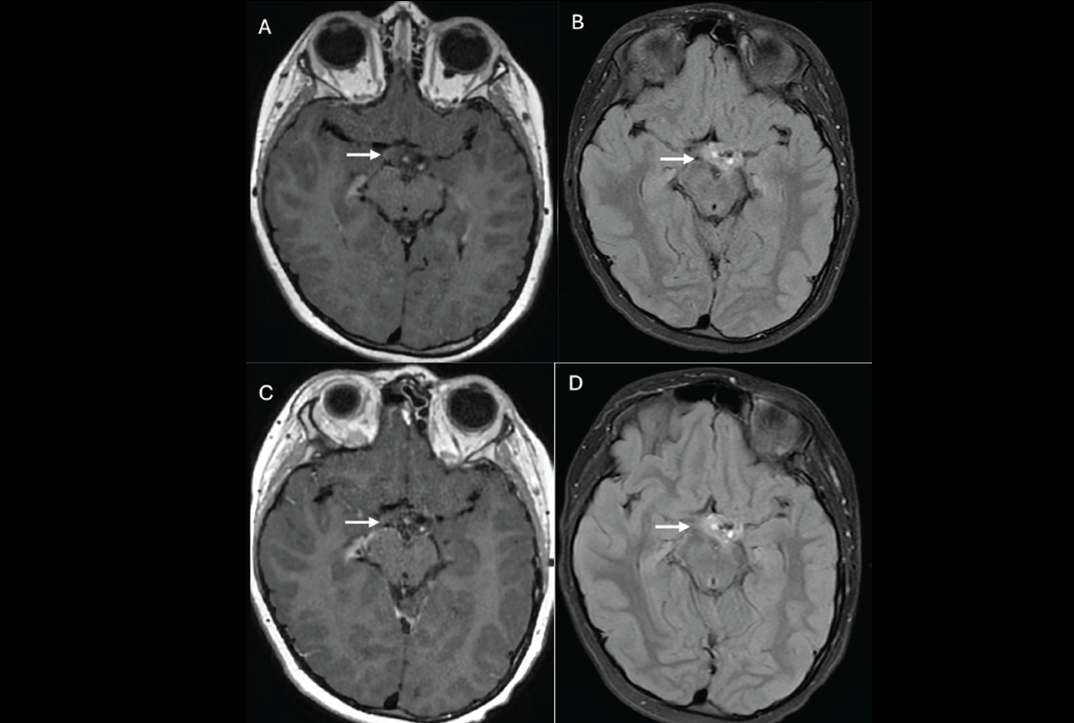

The researchers conducted a study that included data from 340 children from three institutions. Of these, 202 made up an internal, testing/training cohort for the model (105 had GHD and 97 were of short stature), and 138 made up an external validation cohort (61 with GHD and 77 of short stature). They selected 17 radiomics features from pituitary MRI exams using SelectKBest and LASSO (Least Absolute Shrinkage and Selection Operator) and built six machine learning models. The group assessed the models' area under the receiver operating characteristic curve (AUC), sensitivity, specificity, and calibration curves.